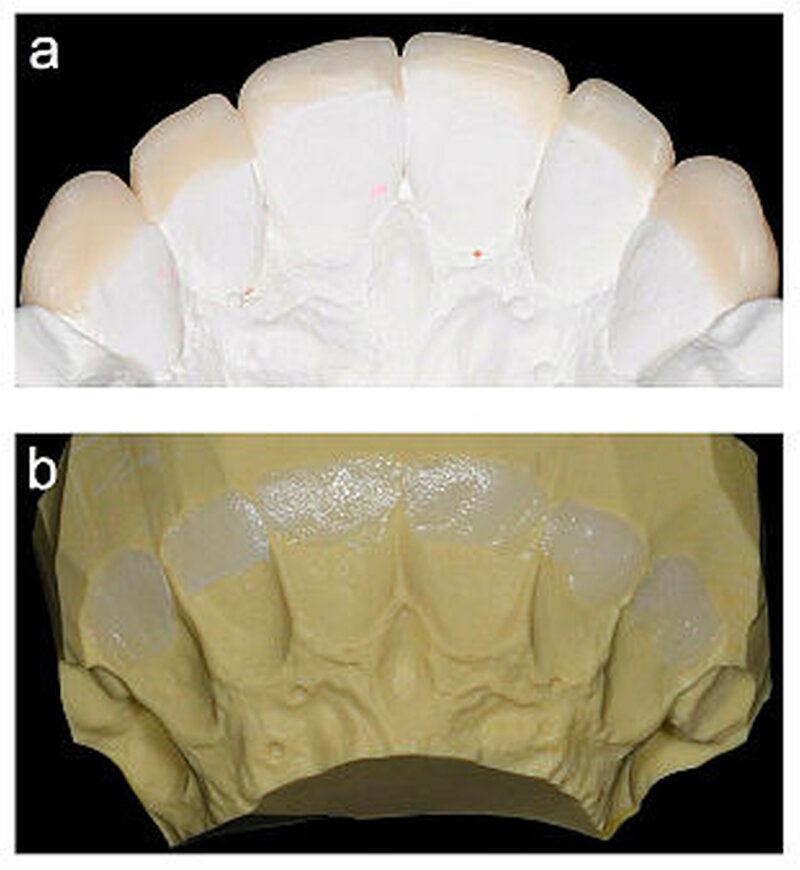

Nach der Bisshebung im Seitenzahnbereich wurden die erosiven Frontzahndefekte im Oberkiefer ebenfalls mit Komposit (Filtek Supreme XTE; 3M Espe) adhäsiv (Optibond FL; Kerr) versorgt. Zunächst wurden die palatinalen Zahnhartsubstanzverluste freihändig mit Komposit aufgebaut (Abbildung 5), daraufhin erfolgte eine Alginatabformung.

Im zahntechnischen Labor wurden die inzisalen Anteile der Zähne aufgewachst, sodass anschließend ein Silikonschlüssel angefertigt werden konnte (Abbildung 6).